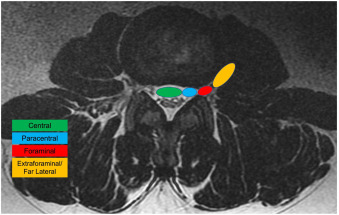

Image Type Lumbar Spine X-Ray CT Scan MRI Scan Anteroposterior (AP) Canal Diameter Cauda Equina Nerve Root Area Conus Medullaris Level Cross-Sectional Area (CSA) of Spinal Canal Disc-Height Index (DHI) Disc Herniation Size Disc Herniation Types Dural Sac CSA Epidural Fat Thickness Filum Terminale Thickness Foraminal Height and Width High-intensity Zone (HIZ) Lateral Recess Width/Depth Modic Endplate Changes (Type I, II, III) Modic (Marrow Signal) Changes Pfirrmann Classification (I-V) Vertebral Bone Quality (VBQ) Score Vertebral Endplate Defects